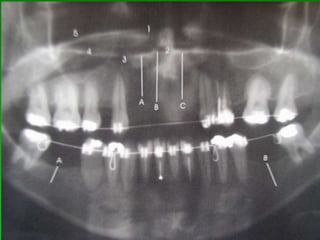

PLANEJAMENTO CIRÚRGICOEXAMES POR IMAGENS:Radiografia Panorâmica para implantes

Seleção do Comprimento e Largura do ImplanteRx PeriapicalRx PanorâmicoTomografia LinearTomografia ComputadorizadaPrototipagemLargura do dente a ser substituido (largura da plataforma protética)Distância dos dentes vizinhos aos espaçosComo regra, usar o maior e mais largo possível

Avaliação Clínica no Momento da Instalação do ImplanteAparelhos especiais Osstell (mede por freqüência e ressonância)Avaliação Clínica (estabilidade)Torquímetro (mínimo 45 Newtons)Avaliação   radiográfica   ( durante   a instalação,  mede  a  distância   entre implantes e estruturas adjacentes)